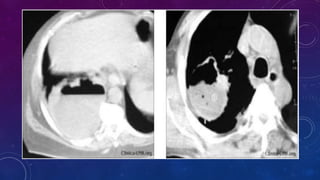

DIAGNOSTICO